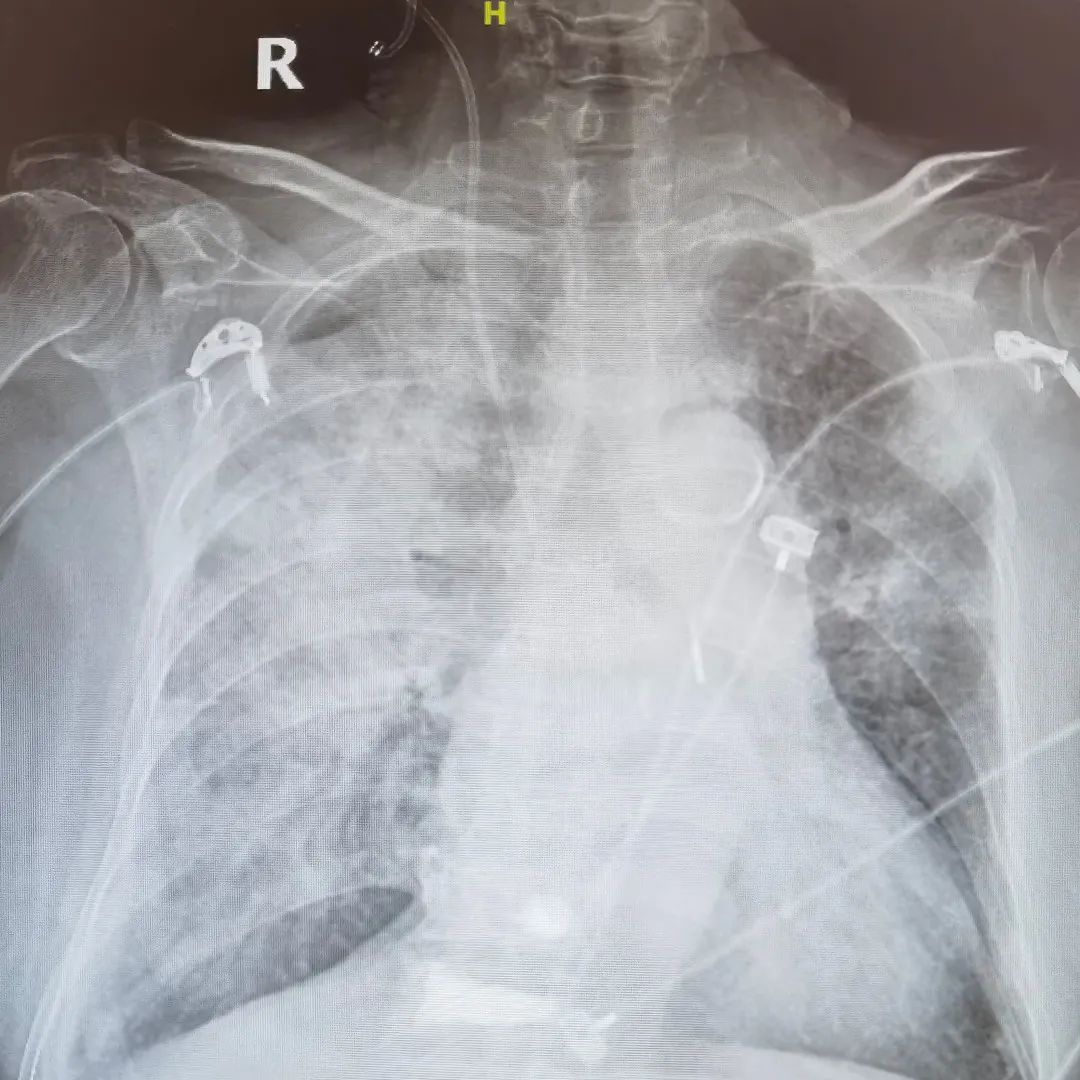

术后继续予冠心病二级预防、利尿、升压、改善心功能等对症支持治疗。因存在急性心肌梗死后机械性并发症,二尖瓣重度反流,床旁胸片提示双肺渗出,循环不稳定,氧饱和度差,于重症监护病房行气管插管,呼吸机辅助呼吸,并床旁CRRT肾脏替代治疗以维持内环境稳态。但患者心功能仍进一步恶化,大剂量血管活性药物泵入仍无法维持血压,遂予床旁植入VA-ECMO。

术前床边胸片

术后48h床边胸片